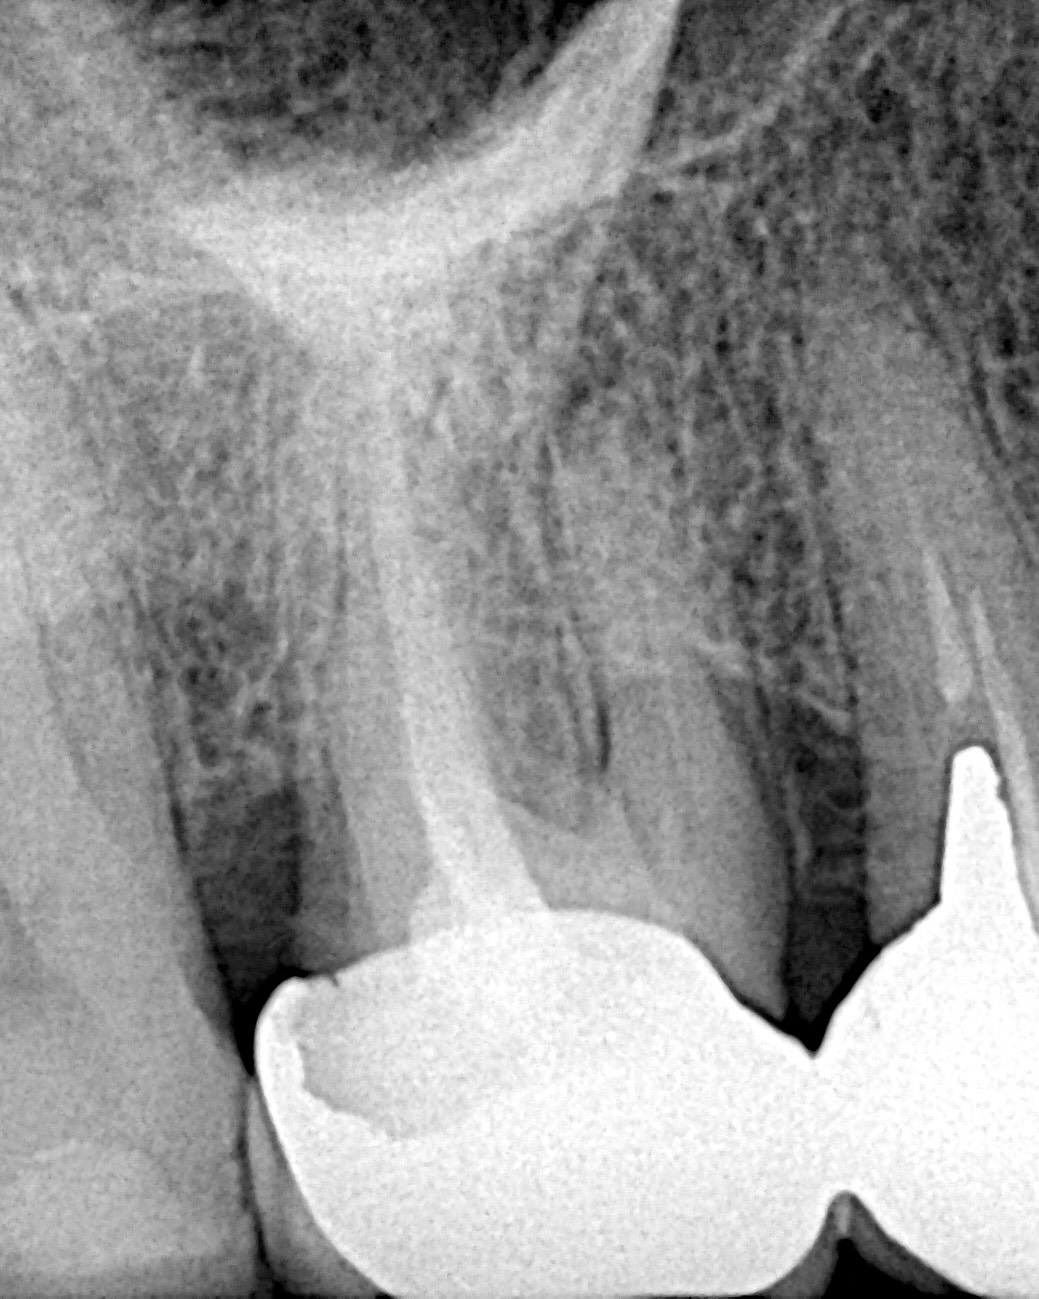

Cu toate astea există și situații când trebuie să refacem un tratament chiar dacă dintele nu prezintă simptomatologie. Intervenția are scop preventiv (dintele să nu devină simptomatic) și este dictată de examenul radiologic de cele mai multe ori (canale ratate, perforații, instrumente fracturate, etc). În acest caz dintele 1.6 avea o coroană veche ce trebuia schimbată. Am analizat radiografia și am observat ca tratamentul endodontic anterior nu putea susține un prognostic bun pe termen lung al dintelui.

Împreună cu pacientul am decis refacerea tratamentului. Astfel obturația endodintica veche a fost îndepărtată, canalele omise au fost reperate, instrumentate și dezinfectate iar la final au fost obturate prin tehnica condensării verticale la cald.